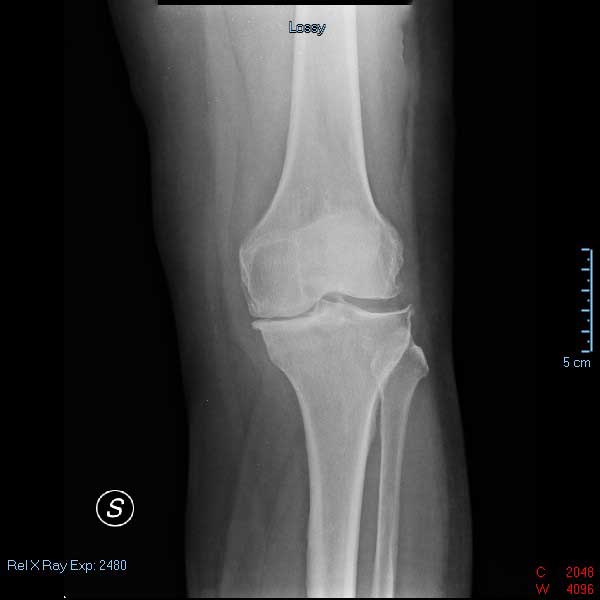

La gonartrosi (l'artrosi di ginocchio) è molto frequente nella popolazione anziana. L’articolazione del ginocchio è molto complessa. Essa è formata da due articolazioni differenti: quella fra femore e rotula e quella fra tibia e femore. Proprio da quest'ultima, generalmente, si ha il diffondersi del processo artrosico che, solo in seconda fase, si va ad estendere al resto dell'articolazione.

Le prime fasi sono spesso asintomatiche e, per tal motivo, diventa difficile diagnosticare (e quindi intervenire) tempestivamente sull'artrosi di ginocchio.

Come nel caso della gonartrosi, anche nella coxartrosi si può rallentare il progredire della malattia, tenendone sotto controllo i sintomi. L'importante è fare una diagnosi precoce, che permetterà al medico ortopedico di studiare la corretta strategia di intervento. L'utilizzo di tecniche di ortopedia rigenerativa, sia per la gonartrosi che per la coxartrosi, da ottimi risultati anche nelle fasi di acuzie della patologia.